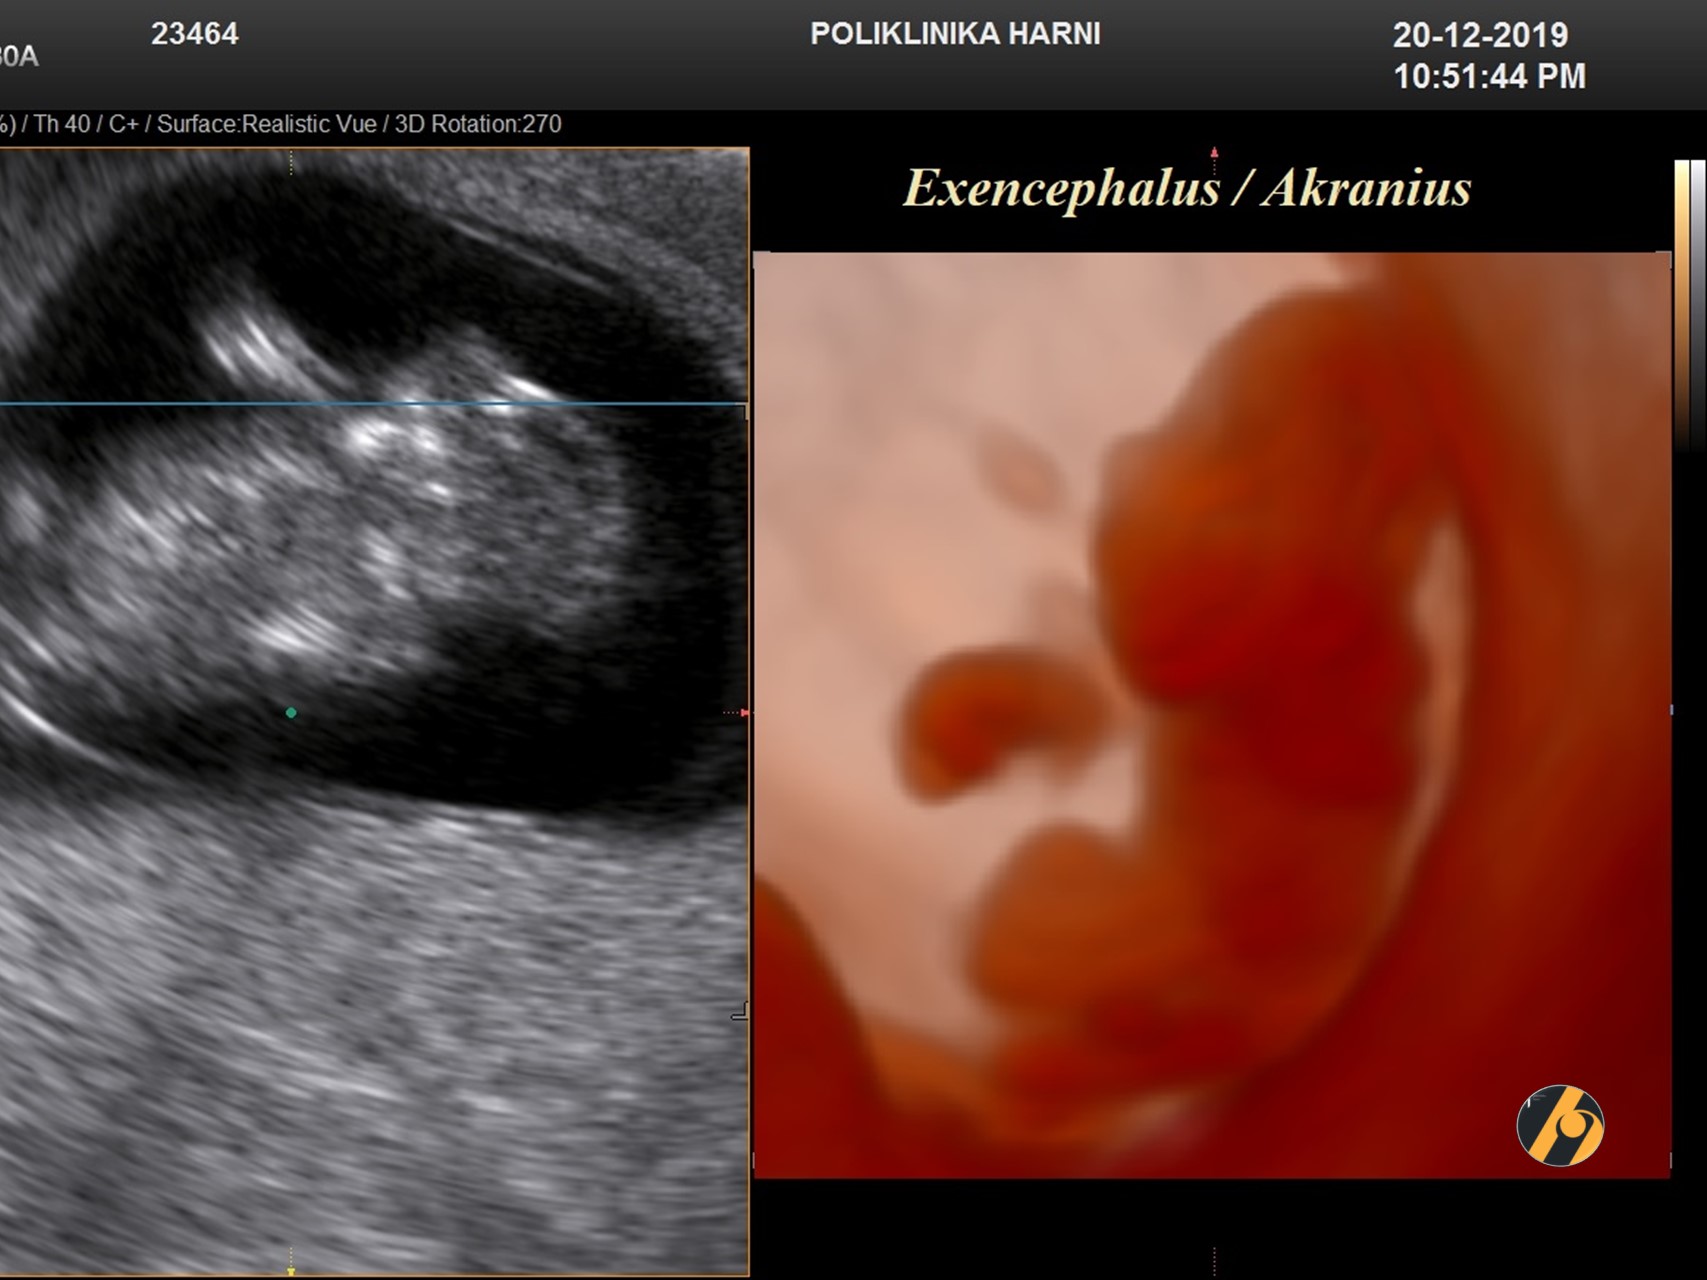

Prevalencija anencefalije je oko 1 na 1,000 rođenih, a etiologija kod više od 90% slučajeva nije poznata.

Dijagnoza anencefalije tijekom drugog tromjesečja trudnoće temelji se na prikazu odsutnosti kranijuma i cerebralnih hemisfera. U prvom tromjesečju se dijagnoza može postaviti nakon 11. tjedna kada se normalno javlja okoštavanje lubanje. Postoji napredovanje od akranijusa do egzencefalije i na kraju anencefalije.